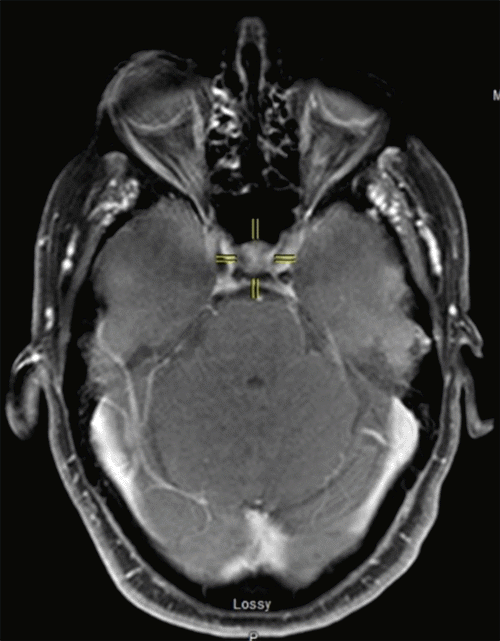

Given the finding of a neuroendocrine tumor, the patient underwent postoperative genetic testing revealing a heterozygous mutation (C.178dupT) within the cyclin-dependent kinase inhibitor 1B (CDKN1B) gene, which is consistent with a diagnosis of MEN4.4,5 At this point attention was turned to the investigation of other endocrine organs. Serum calcium and parathyroid hormone were within normal limits. Neck and thyroid ultrasound (US) showed small cysts within the thyroid but no solid thyroid nodules or parathyroid adenomas. Magnetic resonance imaging (MRI) of the brain revealed mild prominence and heterogenicity of the pituitary, though without any suprasellar extension. This finding was felt to represent pituitary micro-adenoma, though based on biochemical studies in conjunction with history and physical, this lesion was thought to be nonfunctional in nature (Figure 3). Concerning adrenal function, investigation of plasma metanephrines and catecholamines was normal, an appropriate cortisol response was seen in the 1 mg overnight dexamethasone suppression test, and workup for primary hyperaldosteronism was not indicated as the patient was normotensive and without hyperkalemia. Finally, a negative octreotide scan revealed no additional enteropancreatic lesions.

Figure 3. MRI of Head. Published with Permission

Scan displays mild prominence and heterogenicity of the pituitary gland, diagnosed as nonfunctional pituitary adenoma